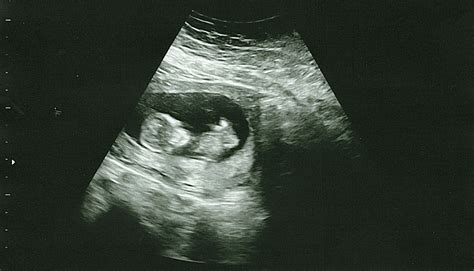

What Can Be Seen on an 8 Week Sonogram?

At 8 weeks, the fetus is still very small, but several key structures can be visualized:

• Gestational Sac: A fluid-filled structure that contains the developing embryo.

• Yolk Sac: A small, round structure that produces blood cells and helps in the early development of the embryo.

• Embryo: The developing fetus, which is about the size of a raspberry at this stage.

• Heartbeat: The fetal heartbeat is usually detectable and can be seen as a rapid flickering on the ultrasound screen.

• Neural Tube: The early stages of the brain and spinal cord can be observed.